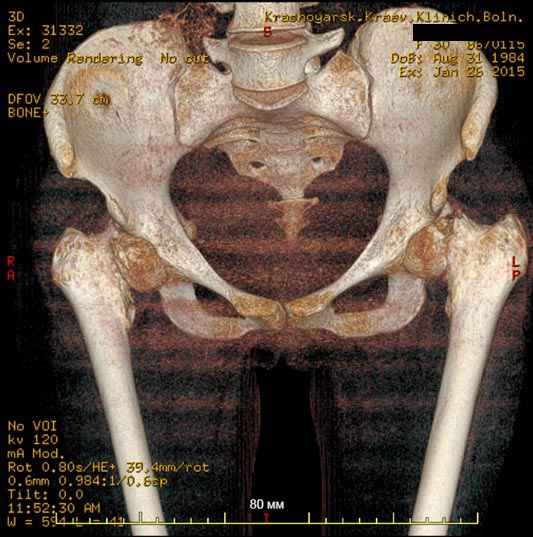

Клинический случай, больная Т. 30 лет, 40 кг, анамнез: Считает себя больной с начала декабря 2014 года, травмы отрицает, ни с чем не связывает. Со слов на фоне полного здоровья появились отеки всего тела, после чего боли в пояснице, правом к/с, затем т/б суставах. Обратилась за мед.помощью по месту жительства, анемия до 40 г/л. Произведена гемотрансфузия эр.взвесью, гемоглобин 100. При обследовании выявлена киста яичника, с подозрением на злокачественный процесс с mts в кости таза пациентка направлена на консультацию к онкологу. Злокачественный процесс исключен.

Направлена на консультацию к гематологу , выполнена стернальная пункция. Данных за миелому не получено. Больная в настоящее время проходит дообследование с перспективой для паллиативного (а может и нет?) протезирования т/б суставов. Из обследований: положительное RW, лечилась 10 лет назад. Гемоглобин 85, снижается, произведена гемотрансфузия до 100, формула б/о. Билирубин общ 47, прямой 9, по УЗИ, ФГС б/о. Т-лимфоциты 60,Т - хелперы - 20. Остальное в пределах нормы, легкие чистые. По МСКТ - дефект правой подвздошной. Как еще обследовать больную? на что похоже? Спасибо заранее за ответы

Не очень понятно насчет патологического характера перелома шеек бедра: на КТ есть локальное разрушение кости?

Кроме очага в подвздошной кости: есть ли другие? В этом может помочь сцинтиография с технецием.